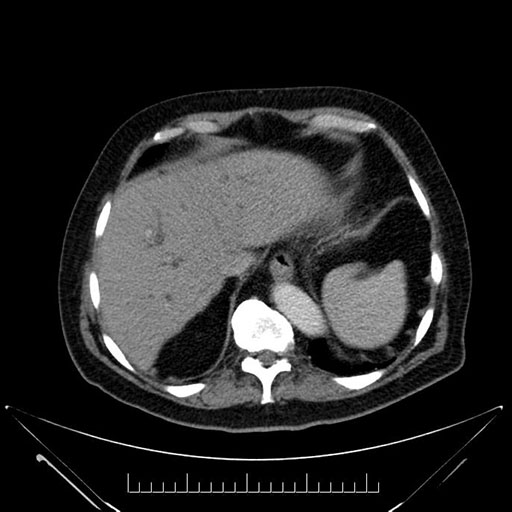

Imaging Analysis

Look through the patient's CT scan to identify any areas of concern for the necessary procedure.

Based on your CT findings, which issue(s) would give reason for "planned slowing down moment(s)" in this case?